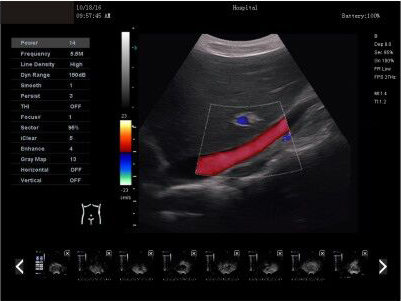

AMAIN Finndu C2 dýralækningaómskoðunarbúnað fyrir meðgöngu